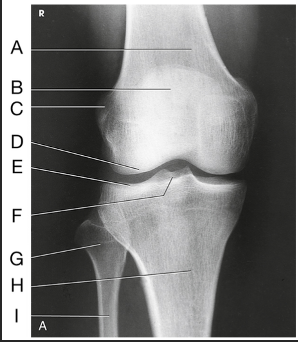

Name this projection.

AP oblique lateral rotation

What is demonstrated?

Medial aspect (distal femur, patella, medial tibial condyles, and fibula)

Label the image: A

femur

Label the image: B

patella

Label the image: C

medial femoral condyle

Label the image: D

lateral femoral condyle

Label the image: E

Lateral tibial plateau

Label the image: F

medial tibial plateau

Label the image: G

medial tibial condyle

Label the image: H

fibula

Label the image: I

tibia